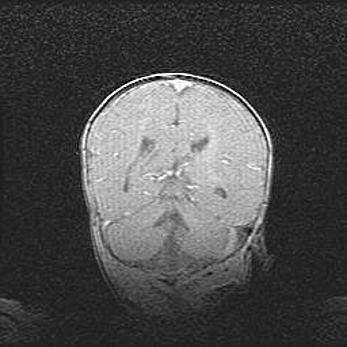

Подострая гематома правой гемисферы мозжечка.

Наружная гидроцефалия.

Возраст: 15 дней

Вес: 3100 г

Пол: женский

Окружность головы: 37 см

Срок гестации: 35-36 недель

При открытой наружной форме гидроцефалии у новорожденных расширяются и переполняются субарахноидные пространства.

Кровоизлияния в мозжечок имеют две клинико-анатомические формы: полушарные гематомы и кровоизлияния в червь.

К появлению этой патологии может привести: повреждения головного мозга, возникающие в результате асфиксии и гипоксии плода при беременности, или травмы во время родов. Редко гематома мозжечка может быть результатом первичной коагулопатии и сосудистой мальформации, диссеминированном внутрисосудистом свертывании, изоиммунной тромбоцитопении.